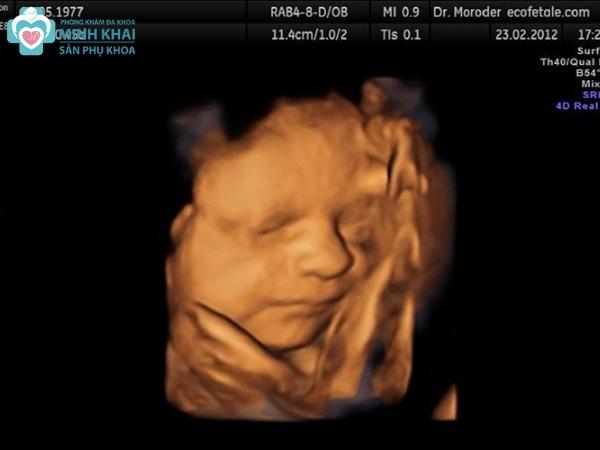

Hình ảnh siêu âm 3D thai nhi tuần 32-40

Ở tháng 8 - 9 cuối cùng của thai kỳ, phân tích hình ảnh siêu âm 3D giúp xác định chuẩn xác các vấn đề bất thường trong cơ thể thai nhi. Các chỉ số sinh học cùng hình ảnh nội soi sẽ cho biết liệu bé có gặp phải các bất thường nguy hiểm như hẹp tá tràng, tắc ruột,... hay không. Bên cạnh đó, các bộ phận hình thành muộn như nhẵn não cũng như hệ thống tuần hoàn của em bé sẽ được thể hiện đầy đủ để bác sĩ có thể đánh giá chi tiết qua thông số động mạch rốn, động mạch tử cung của thai phụ.